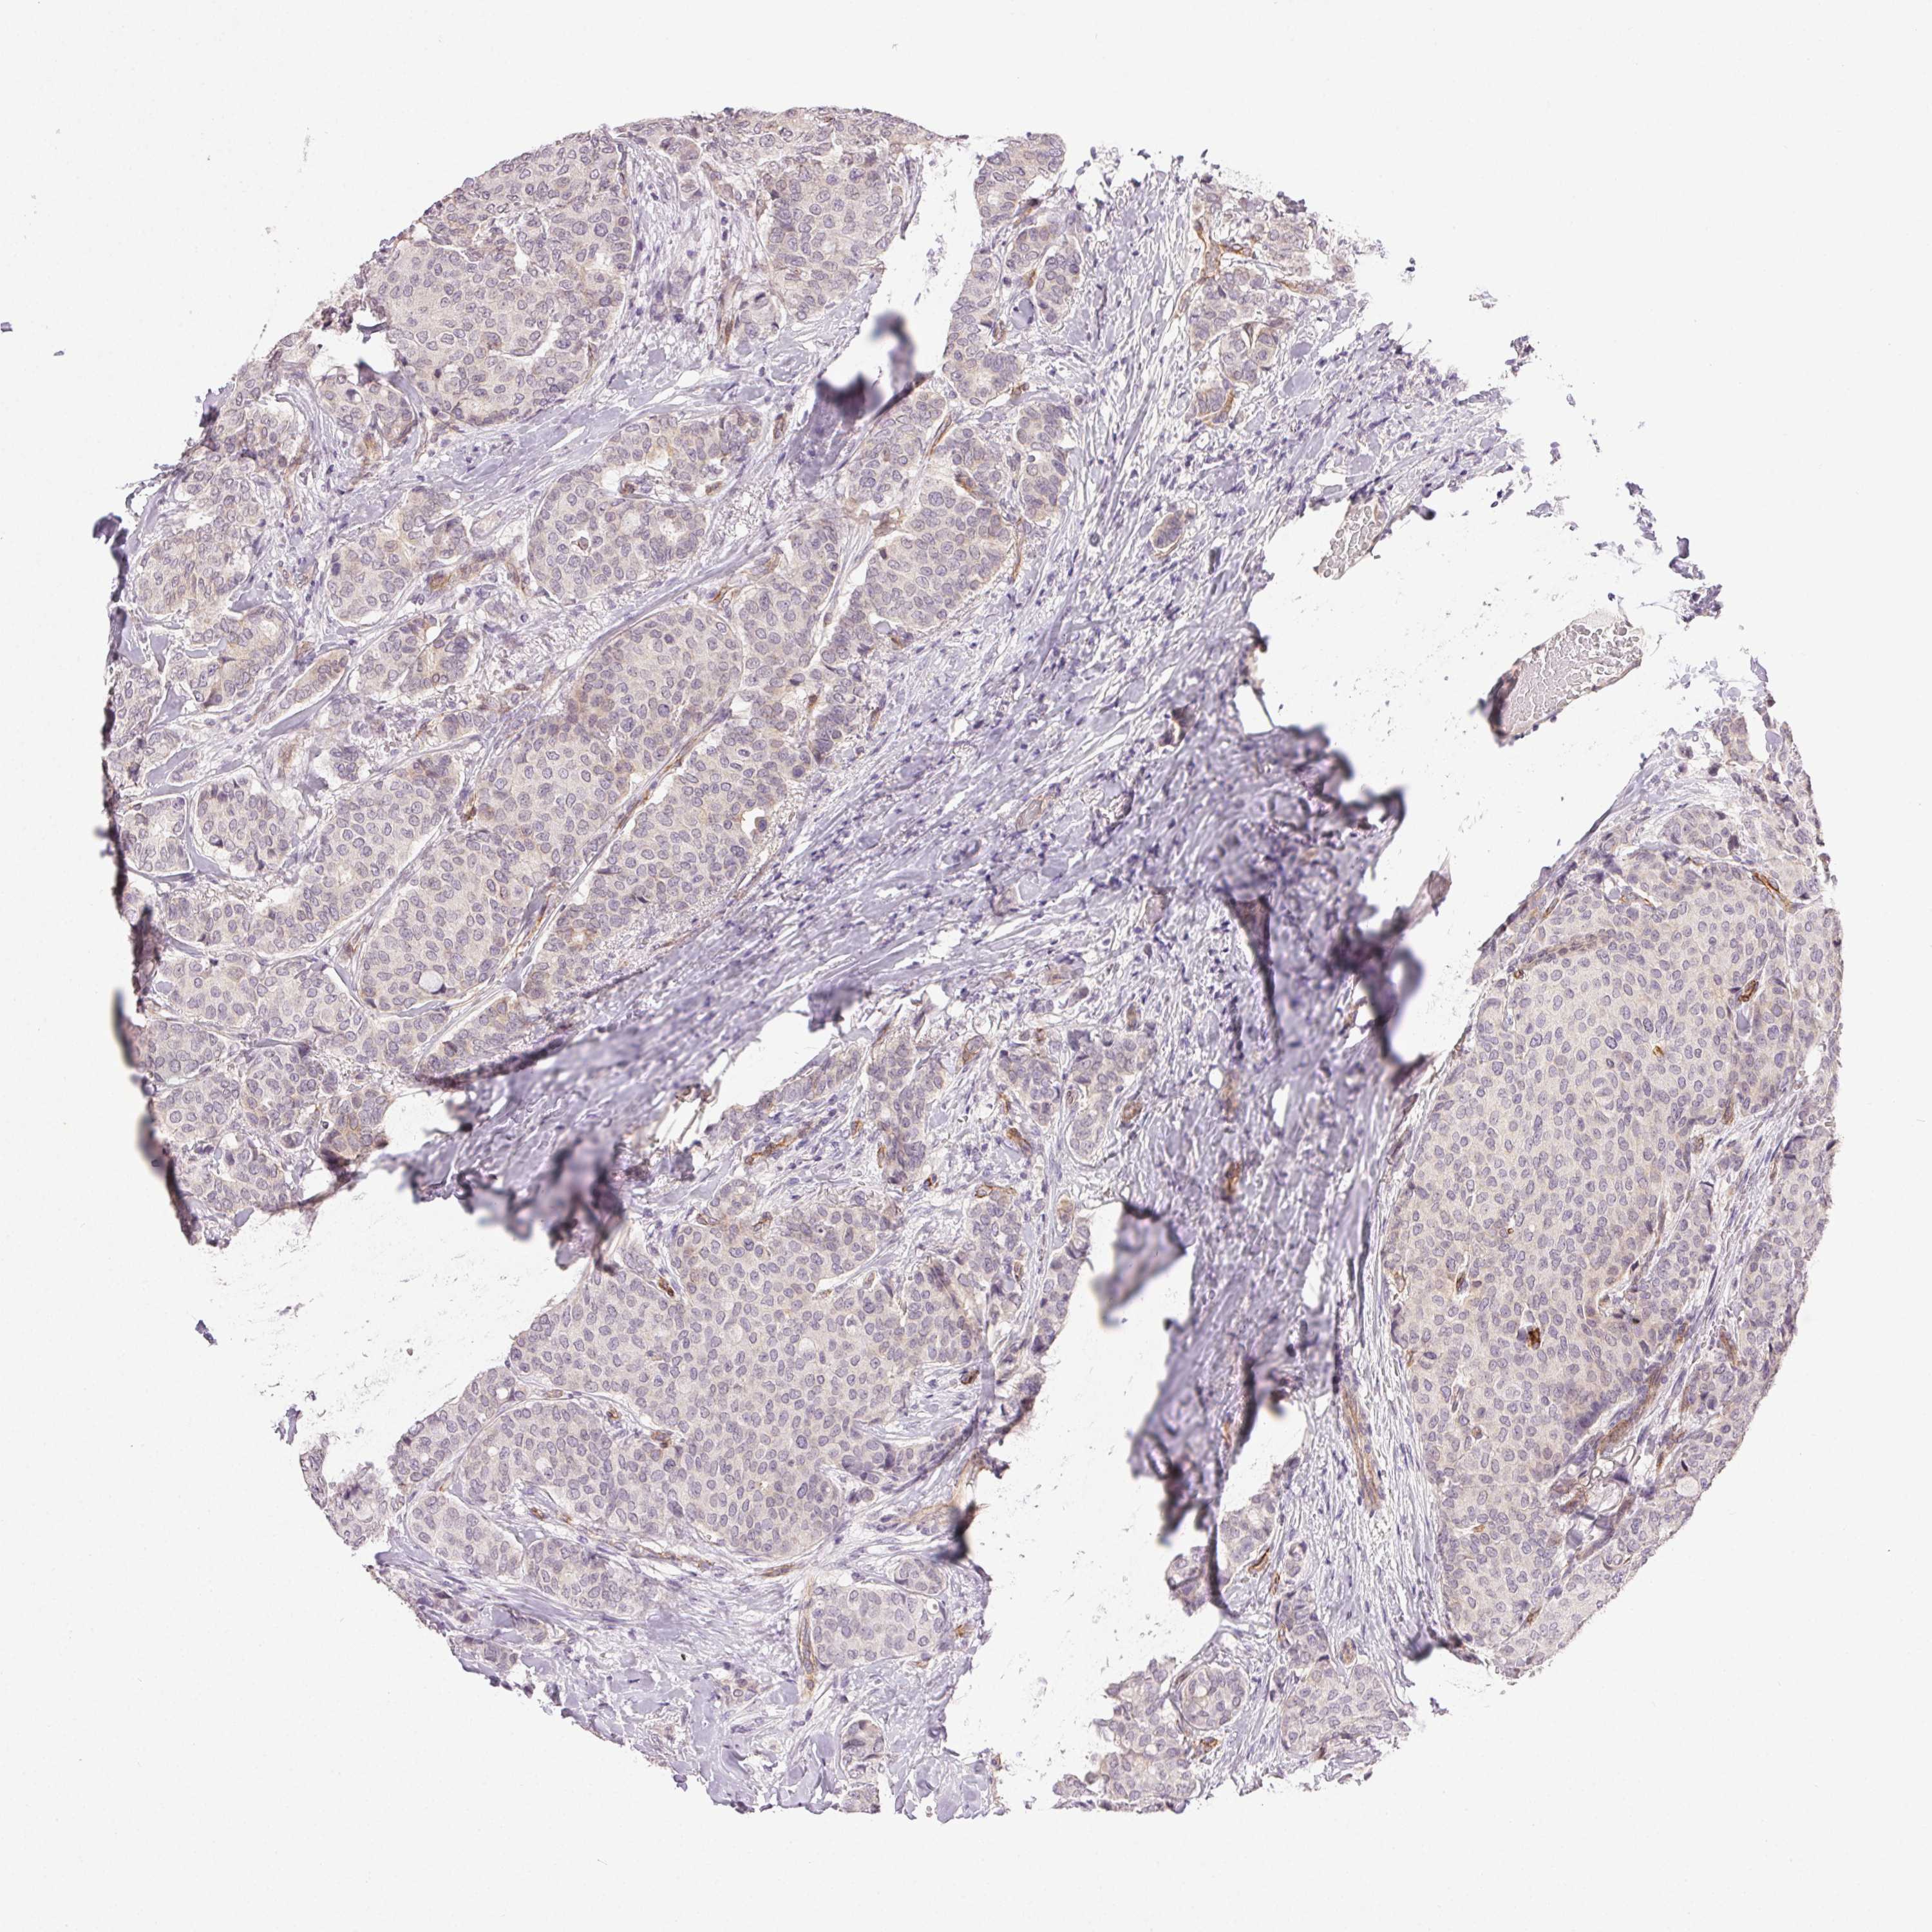

CANCER BREAST CANCER Show tissue menu

BRCA TCGA BRCA VALIDATION PROTEIN EXPRESSION

ANTIBODIES

AND

VALIDATION